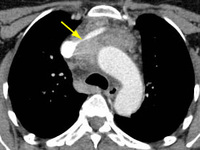

Tomografia computadorizada (TC) do tórax mostrando timoma em estádio III de Masaoka-Koga com comprometimento da parede torácica anterior e invasão da região medial do pulmão esquerdo

Do acervo de Cameron Wright, MD; usado com permissão